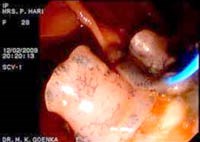

Hình 4

Các ký sinh trùng Fasciola spp. không ra khỏi trong giai đoạn cấp tính của bệnh trước khi chúng trưởng thành, mặc dù các triệu chứng của bệnh nghiêm trọng nhất ở thời điểm này. Ngoài ra, trứng ký sinh trùng có thể không được phát hiện khi các ký sinh trùng đẻ trứng trong các khoảng thời gian, chúng được quan sát thấy trong trường hợp của bệnh sán lá gan mãn tính, hoặc khi các ký sinh trùng này ở vị trí lạc chỗ. Người có thể bị nhiễm sán do ăn thực vật thủy sinh có nhiễm ấu trùng giai đoạn nhiễm metacercaria. Sán lá gan lớn có thể gây ra một loạt các dấu hiệu lâm sàng khác nhau, từ nhiễm trùng không triệu chứng đến xơ gan nặng. Bệnh do Fasciola hepatica có hai giai đoạn: cấp tính (gan) và mạn tính (mật) giai đoạn. Buồn nôn, sốt, đau hạ sườn phải, có hoặc không có kèm theo nổi mề đay được nhìn thấy trong giai đoạn cấp tính.

Hình 5

Tuy nhiên, trong giai đoạn mạn tính, sán và trứng sán có thể gây cản trở đường mật ngoài gan, gây ra các triệu chứng của tắc nghẽn đường mật. Ngoài ra, khi chúng đi vào túi mật có thể gây ra các triệu chứng giống như bệnh lý sỏi mật “cholelithiasis”. Trong đa số trường hợp, chẩn đoán nhiễm như giai đoạn cấp tính hoặc mãn tính rất khó, bởi vì các triệu chứng của cả hai giai đoạn chồng chéo lên nhau. Trong khu vực không phải bệnh lưu hành, các nhà lâm sàng có thể đưa ra chẩn đoán sán lá gan lớn có thể khó khăn và thường bị chậm trễ, vì căn bệnh này không phải là thường gặp. Đôi khi, các triệu chứng có thể bị nhầm lẫn với các bệnh về gan và mật.

Hình 6

Bệnh lý về gan-mật-tụy nhiễm trùng khác cũng có thể xảy ra. Nhiều trường hợp phát hiện sán lá gan lớn ngoài tử cung hay các cơ quan khác trong trường hợp lạc chỗ (ở tinh hoàn, buồn trứng, cơ thẳng bụng, lách, da niêm ở cơ cẳng chân, vú,…) đã được báo cáo trong y văn trên thế giới và Việt Nam. Có những báo cáo về những trường hợp tìm thấy sán ở tim, não, phổi, da, mắt, dạ dày và ruột và được nhắc đến như một ấu trùng di chuyển trong nội tạng (visceral larva migrans_VLMs).